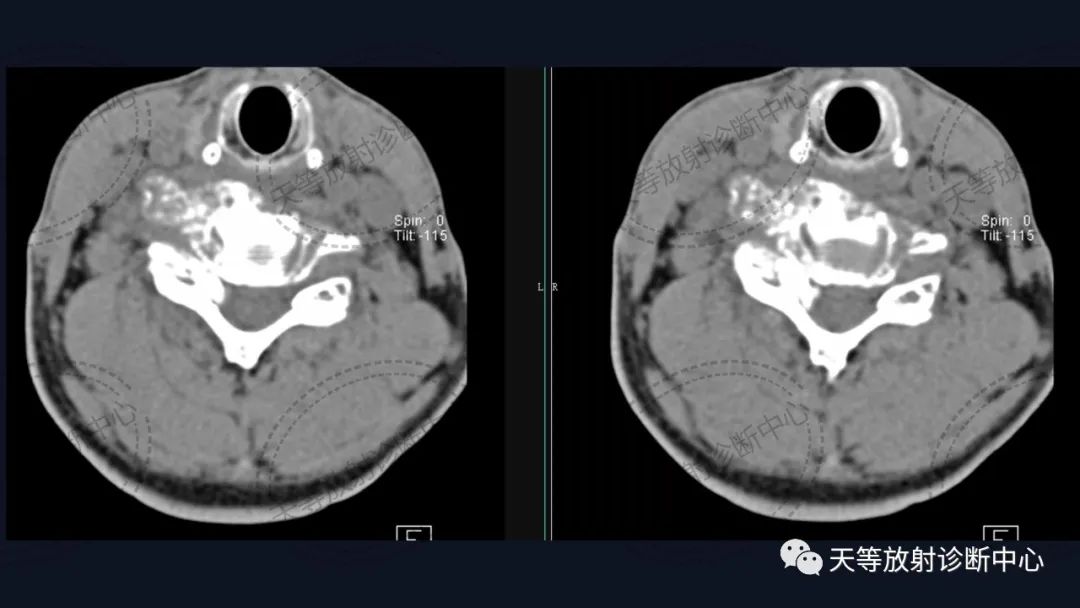

男性,54岁。男性,54岁。

椎体骨质破坏并见大量软骨基质形成

软组织窗骨质破坏呈溶骨性、外生性生长,内部见大量钙化影。

骨质破坏呈溶骨性,大量钙化,肿块向外生长,局部突入椎管内。

病例1:上图:软骨肉瘤。CT显示椎管及其附件骨质溶骨性破坏,椎体周围软组织肿块并含大量钙化影,钙化呈斑片状、斑点状不定型。整个肿块外生性生长为主,局部突入椎管内。